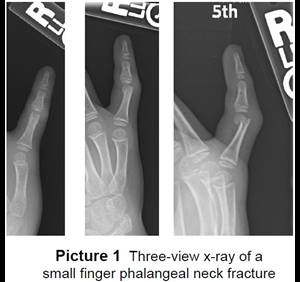

- The surgeon will take an X-ray in the operating room to see the fracture.

- The surgeon will do a closed reduction and/or pinning. Pins are pushed into the skin to hold the pieces of bone together until the they heal (Picture 2). The ends of the pins on the outside of the skin are bent (Picture 3).